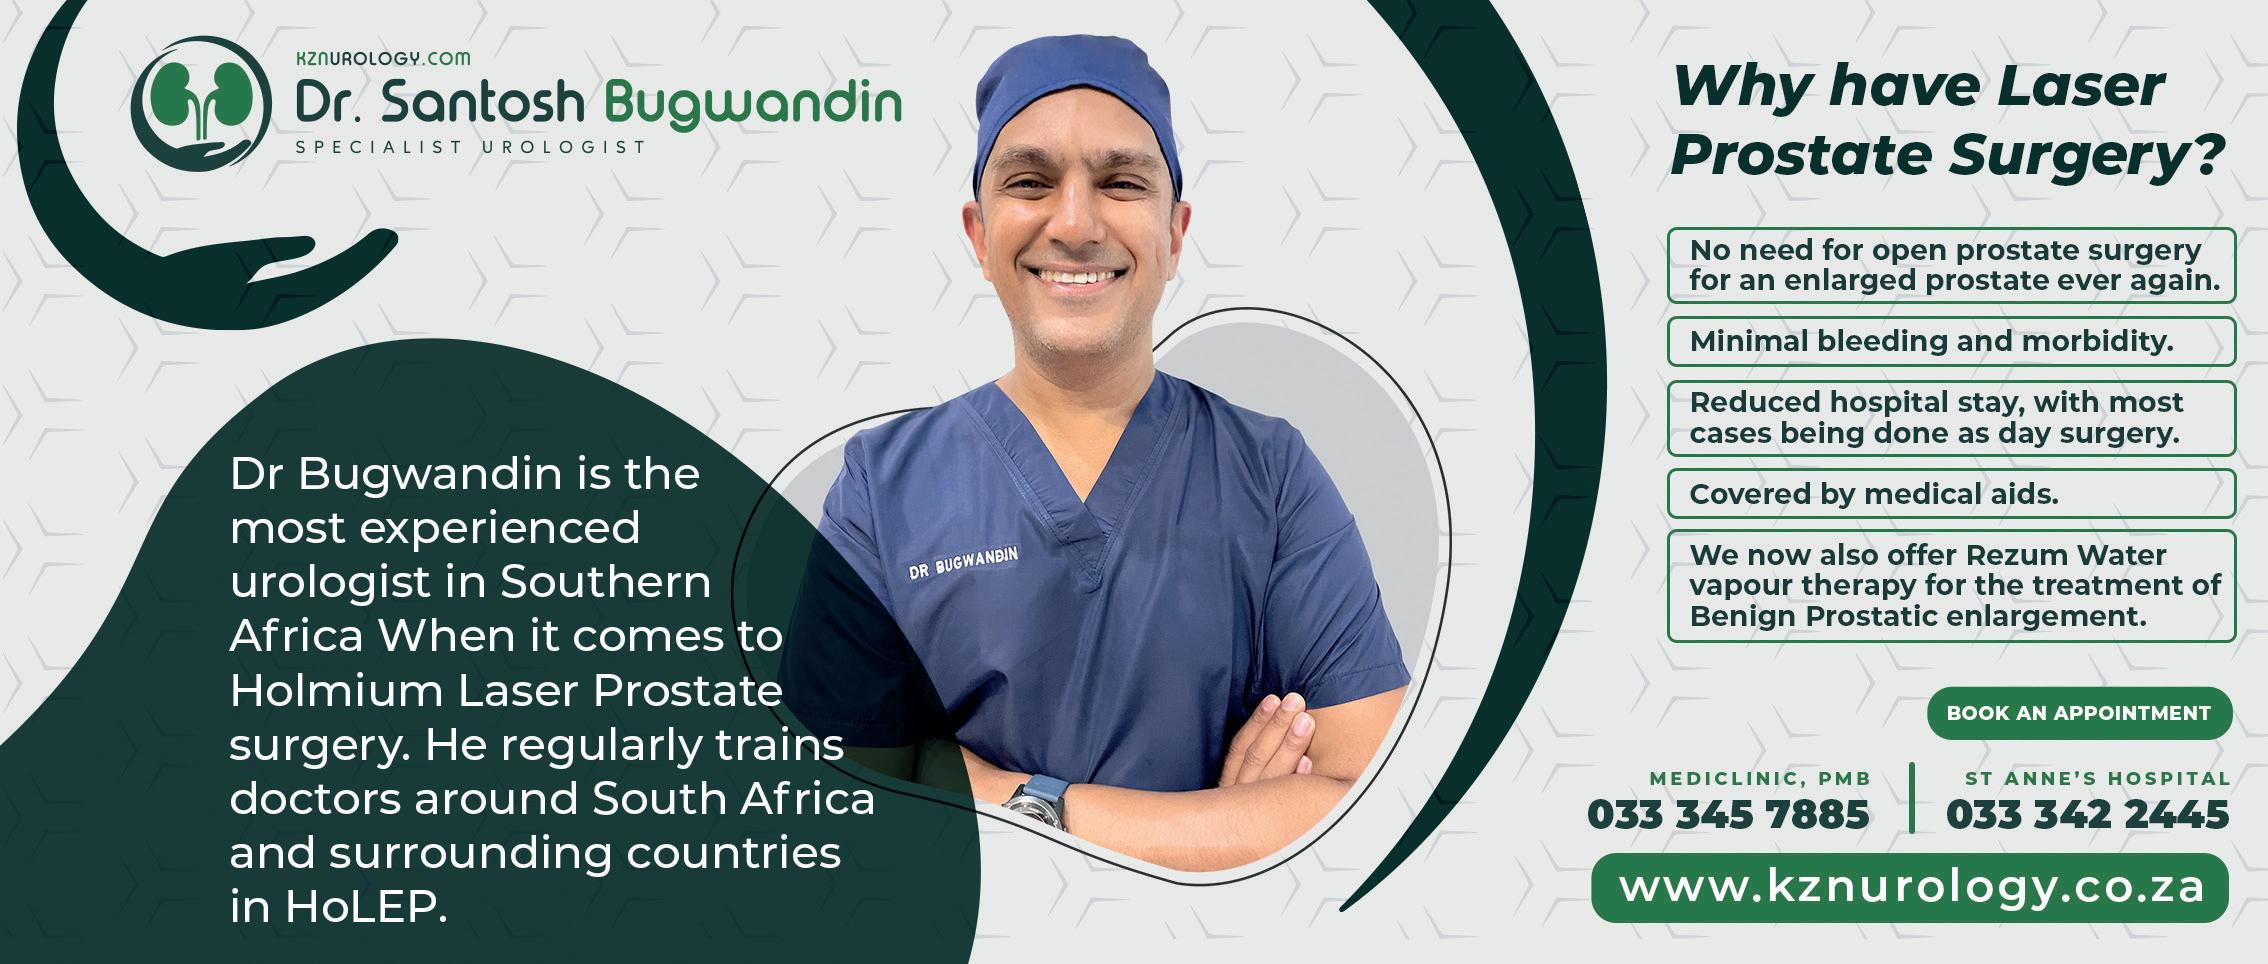

The association between untreated hearing loss, Alzheimer's disease and other types of dementia is an area of intense research. Studies suggest that people with hearing loss are more likely to develop cognitive problems because hearing loss causes brain changes that raise the risk for dementia.

One of the changes caused by hearing loss is “brain shrinkage”. When the auditory cortex of the brain grows inactive, it results in tissue loss and changes in brain structure. The second link between hearing loss and dementia is “brain overload”. When it’s difficult to hear, the brain must work overtime just to understand what people are saying. Straining to hear all day depletes a person’s mental energy and steals brain power needed for other crucial functions like remembering, thinking and acting.

The third link between hearing loss and Alzheimer’s is social isolation. A study by the National Council on the Aging (NCOA) found that people with untreated hearing loss are more likely to experience loneliness, depression and anxiety and are less likely to engage in social activities. When a person withdraws from life, their risk for dementia intensifies. In short, the less we stimulate our brains by using it to hear and listen, the quicker our brain function declines, putting us at greater risk for dementia.

If a loved one is having trouble understanding speech

and finding simple conversations exhausting, help them to get their hearing checked sooner rather than later. Hearing loss has some of the same symptoms as cognitive impairment. Sometimes, undiagnosed hearing loss symptoms are mistakenly thought to be indicators of Alzheimer’s and dementia.

A hearing test is the only way to confirm hearing loss, and, once confirmed, it is important to know that the person is at a higher risk of developing dementia. The earlier hearing loss is identified the sooner one is able to engage in treatment plans to help minimise the risk of cognitive decline.

A treatment plan may include taking medications as recommended, staying active and socially engaged, and wearing hearing aids. Numerous studies have shown that hearing aids not only improve a person’s hearing but also help preserve a person’s independence, mental abilities, and emotional and physical health, and encourage social interaction. A hearing impairment escalates feelings of confusion, disorientation and isolation. Hearing aids can help relieve Alzheimer’s symptoms by making communication easier and slowing the rate of memory decline by keeping your brain active.

KATE-MARIE is a qualified hearing aid acoustician with over 12 years of experience working in the hearing healthcare industry. She runs her own private practice with rooms in Howick (Lenmed Howick Hospital Complex), Hilton (Hilton Life Hospital Complex) and Pietermaritzburg (Hayfields). katebutlin77@gmail.com